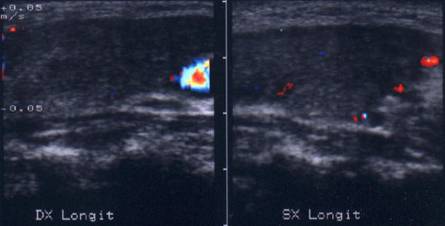

Lob drept, proiectie trasversala. Lob

stang, proiectie trasversala.

Lob drept, proiectie longitudinal. Lob stang, proiectie longitudinala.

Femeie de 41 ani. Tiroida de consistenta dura, foarte

dureroasa la palpare, cu suprafata neregulata.

Ecografia: moderata crestere a volumului; marginile lobilor rau definite; structura

intens ne mogena cu alternanta de arii hipoecogene, de edem si altele intens ecogene,

cu aspect pseudonodular.

Examene de laborator: moderat hipertiroidism; indici de fibroza foarte ridicati.